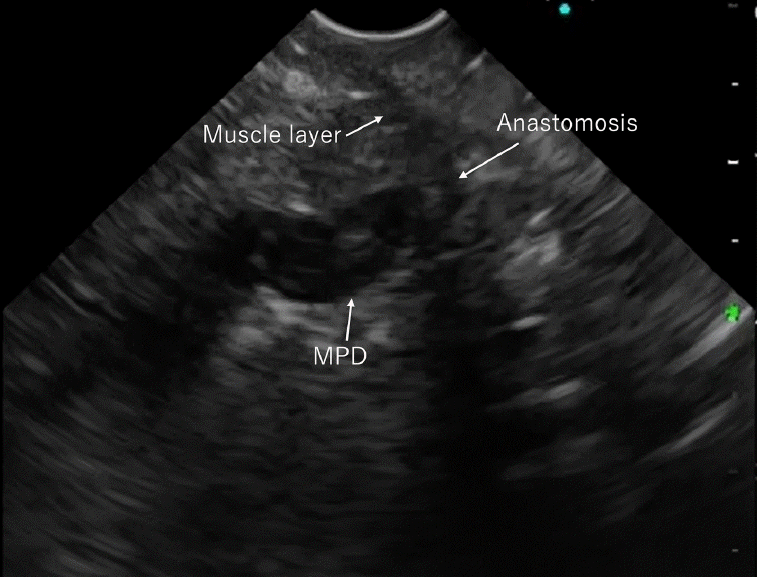

The anastomotic site was carefully examined using EUS (Fig. 3). The main pancreatic duct (MPD) was dilated, making it clear to visualize, and the pancreatic parenchyma and muscle layer of the jejunum were identified. The MPD was then punctured at its end, appearing as the closest point to the endoscope in the EUS image (this point represents the opening of the MPD into the anastomosis line), which ensures puncture through the anastomosis, not the parenchyma.

Fig. 2.

Endoscopic ultrasound-guided pancreaticojejunostomy procedure steps. (A) A colonoscope inserted into the afferent jejunal limb till the pancreaticojejunal anastomosis. (B) After endoscopic retrograde pancreatography failure, a guidewire is left in the jejunum, and the scope is exchanged. (C) A forward-viewing echoendoscope is inserted over the guidewire until anastomosis is achieved. (D) The pancreatic duct is punctured using a fine needle aspiration needle, and a guidewire is inserted. (E) Tract dilation using Tornus ES drill dilator. (F) Finally, a fully covered self-expandable metal stent is deployed inside the pancreatic duct across the anastomosis.